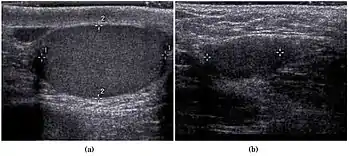

Fig. 3. Seminoma. (a) Seminoma usually presents as a homogeneous hypoechoic nodule confined within the tunica albuginea. (b) Sonography shows a large heterogeneous mass occupying nearly the whole testis but still confined within the tunica albuginea, it is rare for seminoma to invade to peritesticular structures.

Approximately 95% of malignant testicular tumors are germ cell tumors, of which seminoma is the most common. It accounts for 35%–50% of all germ cell tumors. Seminomas occur in a slightly older age group when compared with other nonseminomatous tumor, with a peak incidence in the forth and fifth decades. They are less aggressive than other testicular tumors and usually confined within the tunica albuginea at presentation. Seminomas are associated with the best prognosis of the germ cell tumors because of their high sensitivity to radiation and chemotherapy.

Seminoma is the most common tumor type in cryptorchid testes. The risk of developing a seminoma is increased in patients with cryptorchidism, even after orchiopexy. There is an increased incidence of malignancy developing in the contralateral testis too, hence sonography is sometimes used to screen for an occult tumor in the remaining testis. On US images, seminomas are generally uniformly hypoechoic, larger tumors may be more heterogeneous [Fig. 3]. Seminomas are usually confined by the tunica albuginea and rarely extend to peritesticular structures. Lymphatic spread to retroperitoneal lymph nodes and hematogenous metastases to lung, brain, or both are evident in about 25% of patients at the time of presentation.